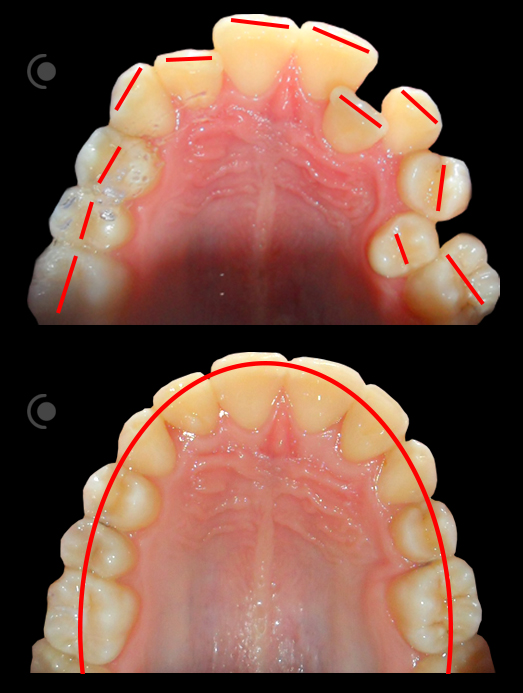

O našoj kvaliteti najbolje govore naši rezultati!